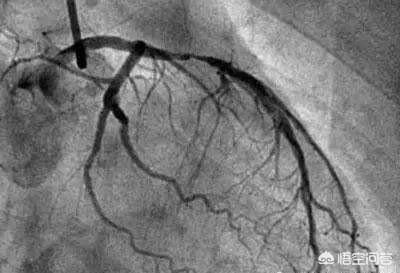

最も大きな割合を占める心臓画像検査は、冠動脈疾患の診断に用いられるゴールドスタンダード、冠動脈造影検査です。近年、わが国の冠状動脈性心臓病の罹患率はますます高くなり、ますます若くなり、当然のことながら冠状動脈造影はますます行われ、省および市の循環器内科病院では冠状動脈造影は一般的な食事であり、いくつかの郡病院でも冠状動脈造影だけでなく、冠状動脈インターベンション治療が数多く行われています。医師と患者は冠動脈造影に慣れているが、結局、体にどんな害があるのだろうか?我々は、冠動脈造影を行う方法を理解するために一緒に来る?何が危険なのか?解決策は?

- 造影剤は冠動脈を "照らす":人体の冠動脈は比較的小さく、冠動脈の主幹はわずか5、6ミリ、太い枝の一部は2、3ミリ程度、残りはさらに細い枝で、これらの血管は周囲の組織とつながっており、その手前は骨や筋肉などで覆われている。そこで、冠動脈造影を行う際には、先ほどのカテーテルの中から造影剤を注入し、冠動脈を造影剤で満たします。造影剤はX線不透過性の薬剤で、冠動脈造影の際に冠動脈を "明るく "照らし、冠動脈の分布、大きさ、狭窄や閉塞の有無をはっきり見ることができる。

- DSA(Digital Subtraction Angiography)とは血管を撮影するカメラである:先に述べた冠動脈の写真を撮るための装置がDSAであるが、実はこれもX線検査の一種であり、造影剤を注入しながら様々な冠動脈を多角的に、まさに360度の死角とも言える角度から写真や動画を撮影・記録することができ、これらの写真や動画はCD-ROMに預けることができるので保存や解析が容易である。冠動脈造影が冠動脈疾患を診断するためのゴールドスタンダードであるのは、冠動脈造影がこれほど鮮明な写真やビデオを撮ることができるからである。

冠動脈造影検査は、大腿動脈の位置から針を刺し、冠動脈の位置までチューブを通し、ヨード造影剤を打ち込んで冠動脈を映し出し、冠動脈の先天性疾患、アテローム性動脈硬化症、動脈瘤、動脈奇形などを診断するもので、その多くは内腔の狭窄をもたらすアテローム性動脈硬化症である。狭窄の程度を評価することができ、心筋梗塞を伴う重度の狭窄の場合は、治療目的で狭窄した内腔を広げて血流を回復させるためにステントを直接挿入することができる。